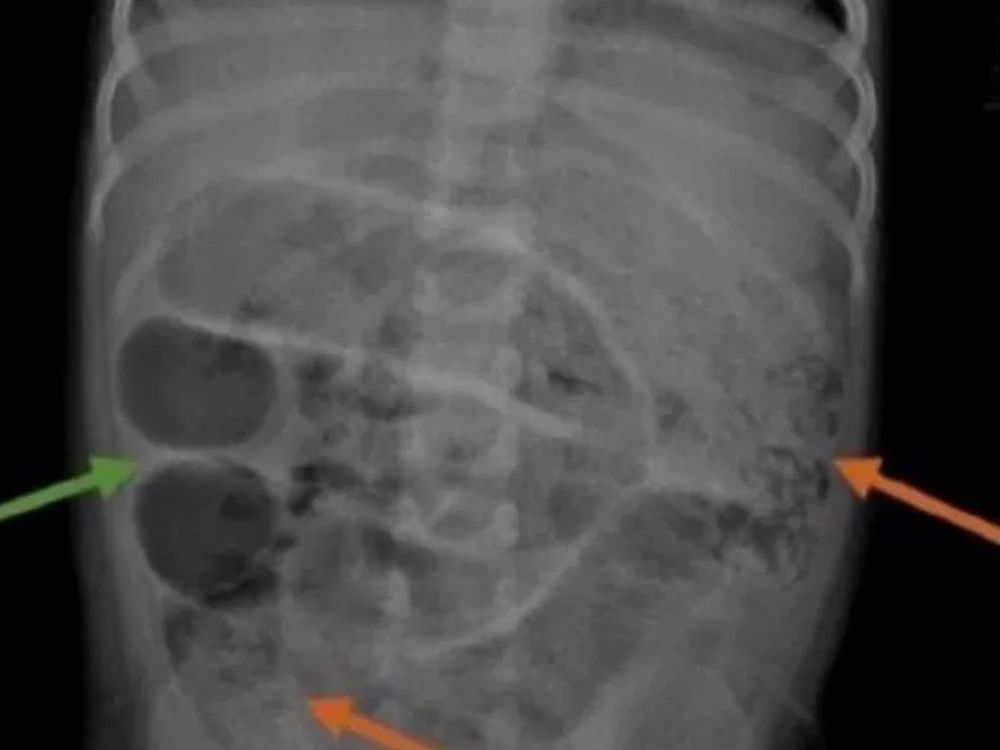

Kasus medis mengejutkan terjadi di Jember, Jawa Timur, di mana seorang anak laki-laki berusia 3 tahun mengalami kondisi serius akibat infeksi cacing gelang (Ascaris lumbricoides). Dokter menemukan cacing hidup sepanjang 35 cm di dalam usus anak tersebut, yang menyebabkan sumbatan dan membahayakan nyawanya. Apa penyebab dan bagaimana para orang tua dapat mengantisipasi hal ini? Yuk, simak penjelasannya di bawah.

Cacing gelang adalah sejenis cacing parasit yang hidup di usus manusia, khususnya anak-anak. Ukurannya bisa mencapai 20–35 cm dan jumlahnya bisa banyak jika tidak segera ditangani. Cacing ini termasuk jenis yang paling umum menginfeksi manusia, terutama di daerah dengan sanitasi buruk.